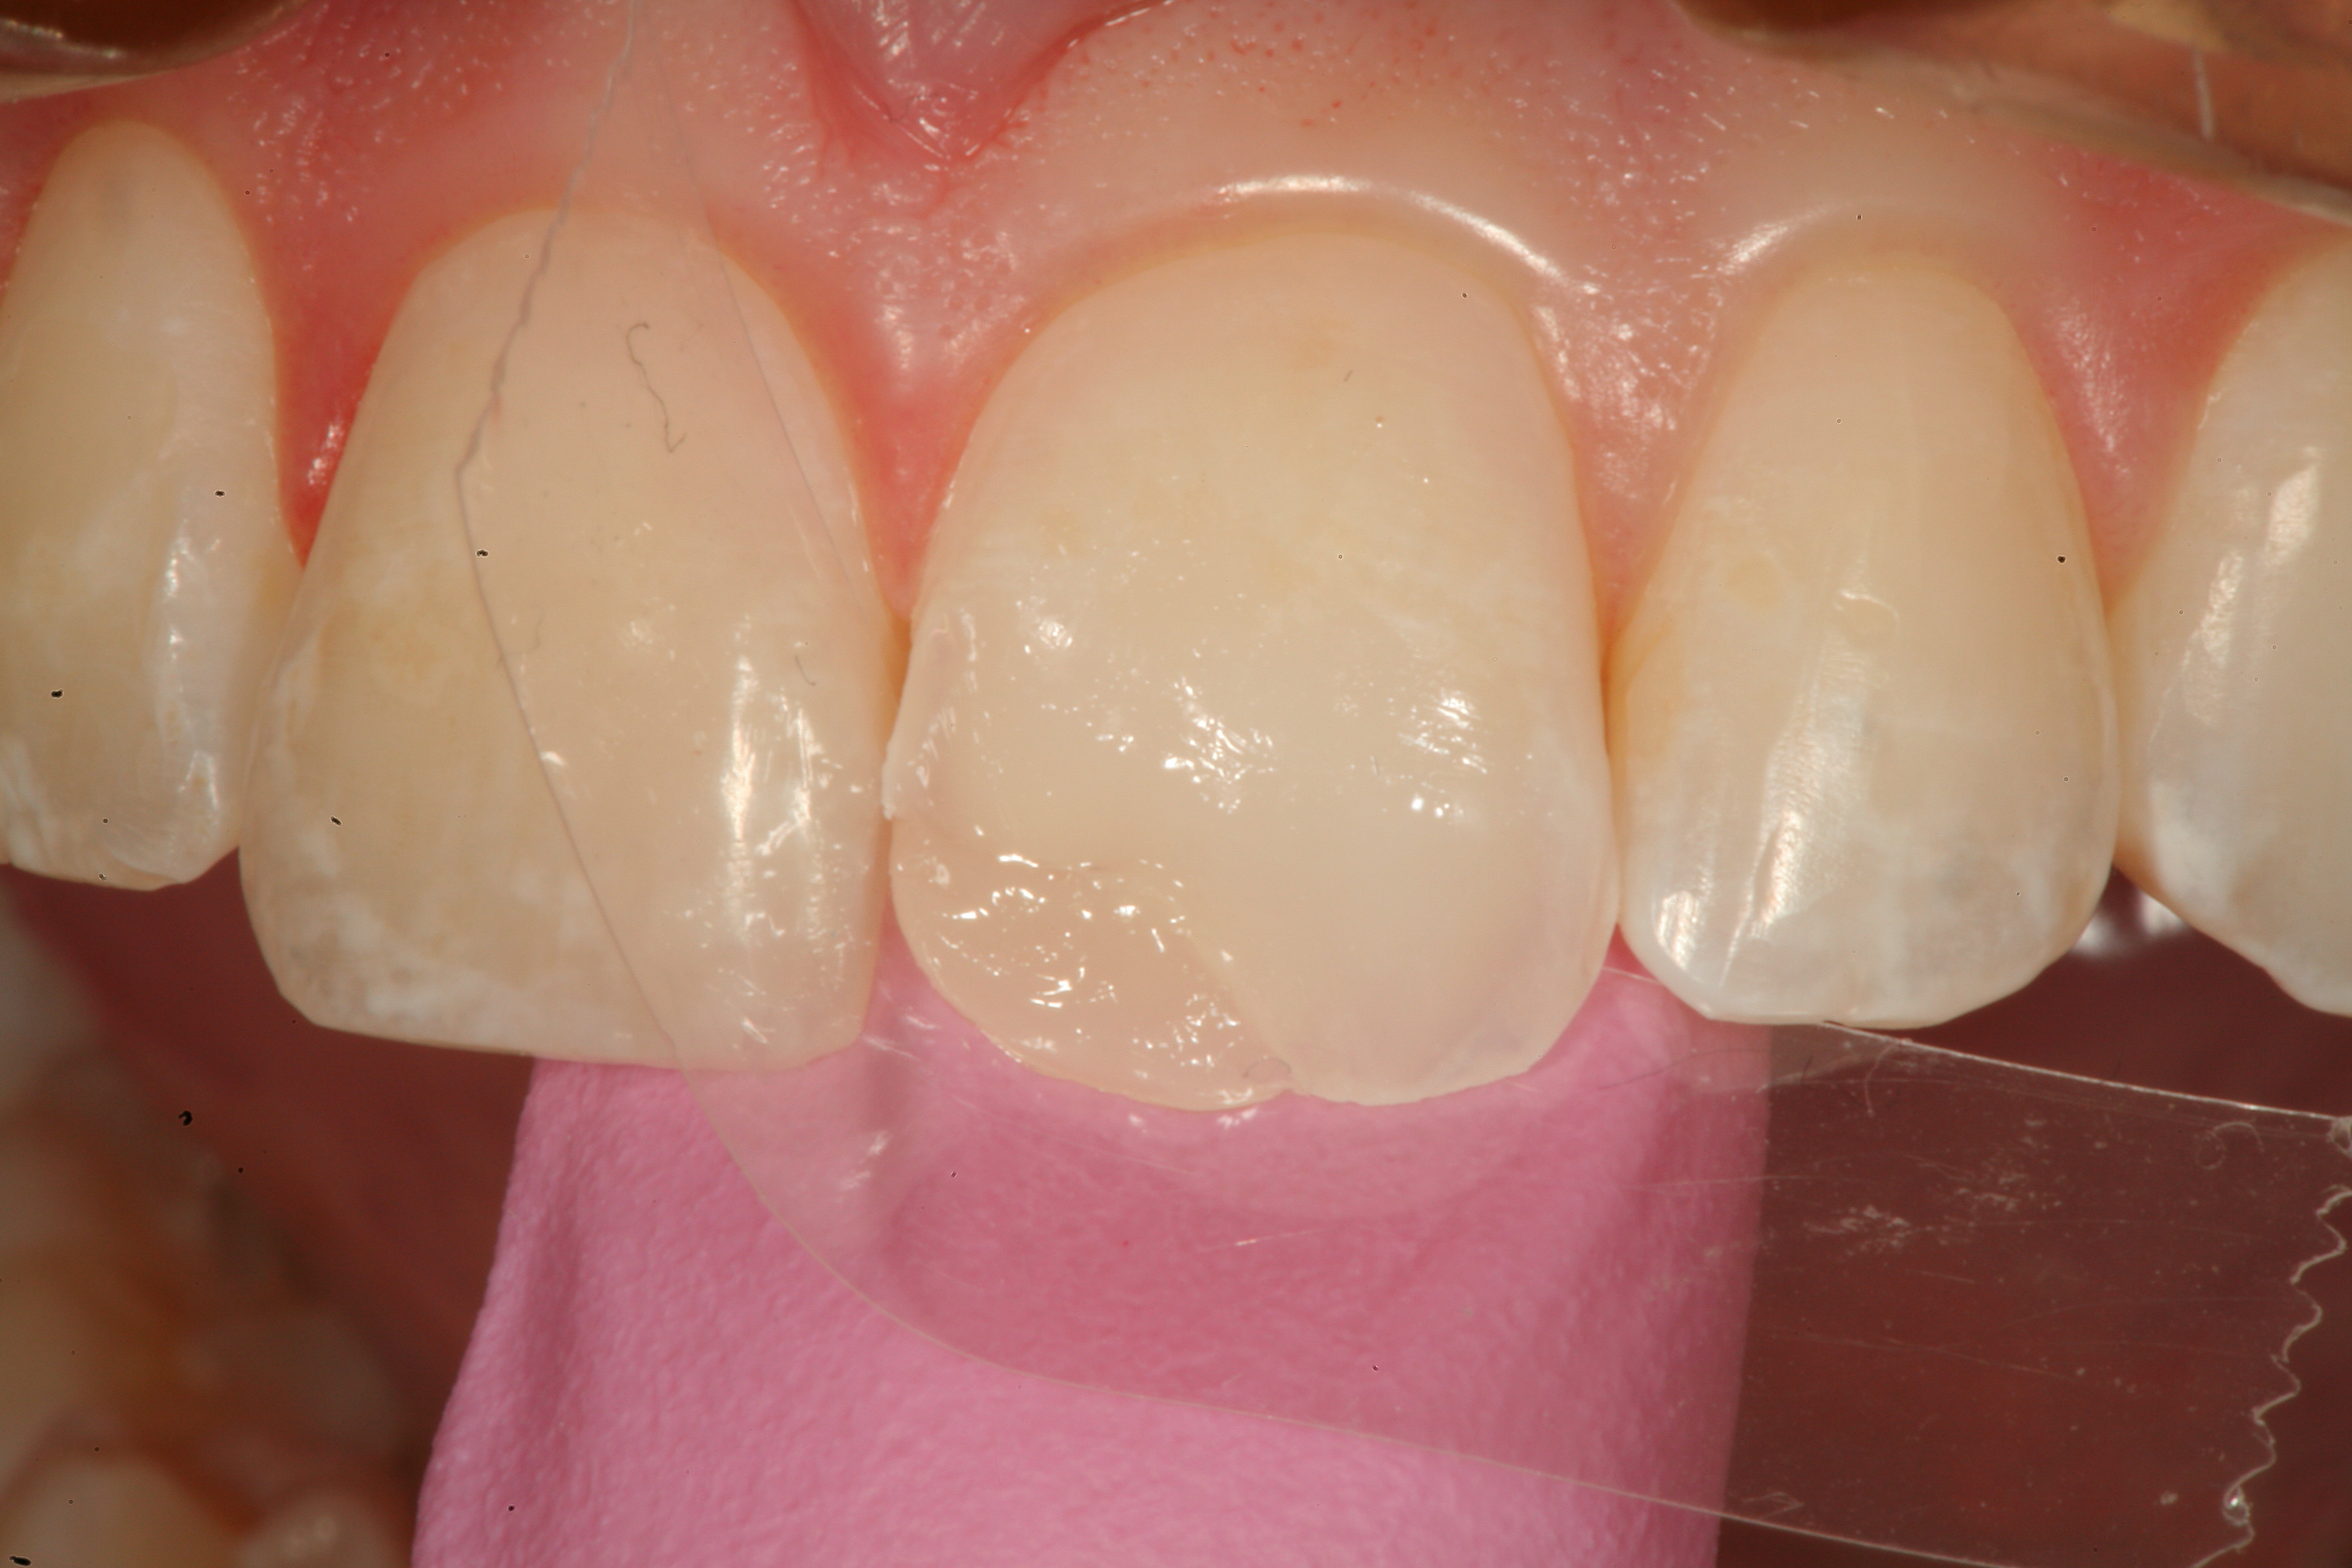

Fig 12. A Class IV mesial incisal fracture is shown from the facial aspect on tooth No. 9.

Figure 12

Fig 13. After placement of a bevel on the facial surface 2 to 3 mm from the position of the fracture, the enamel is etched and rinsed, and an adhesive resin is scrubbed into the prepared surface.

Figure 13